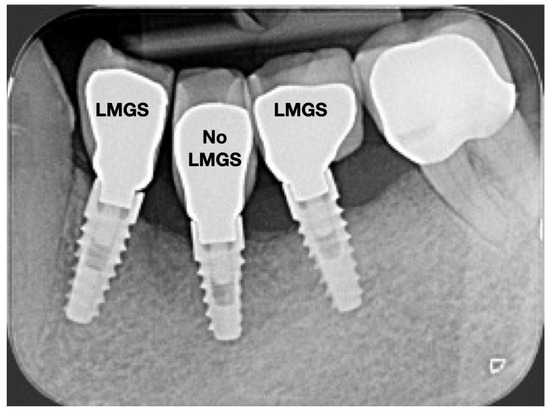

A total of 164 LMGS implants (37.4%) and 195 no-LMGS implants (42.1%) presented PIM. Differences between LMGS implants and no-LMGS implants were not statistically significant (p > 0.05). A total of 28 (6.3%) LMGS implants and 98 (21.1%) no-LMGS implants demonstrated P with a statistically significant difference (p < 0.01). Figure 2, Figure 3, Figure 4 and Figure 5 report examples of radiographs during follow-up.

Figure 2.

Radiograph of three (3) implants at crown delivery. (LMGS = with a laser-microgrooved collar surface; No-LMGS = without a laser-microgrooved collar surface).